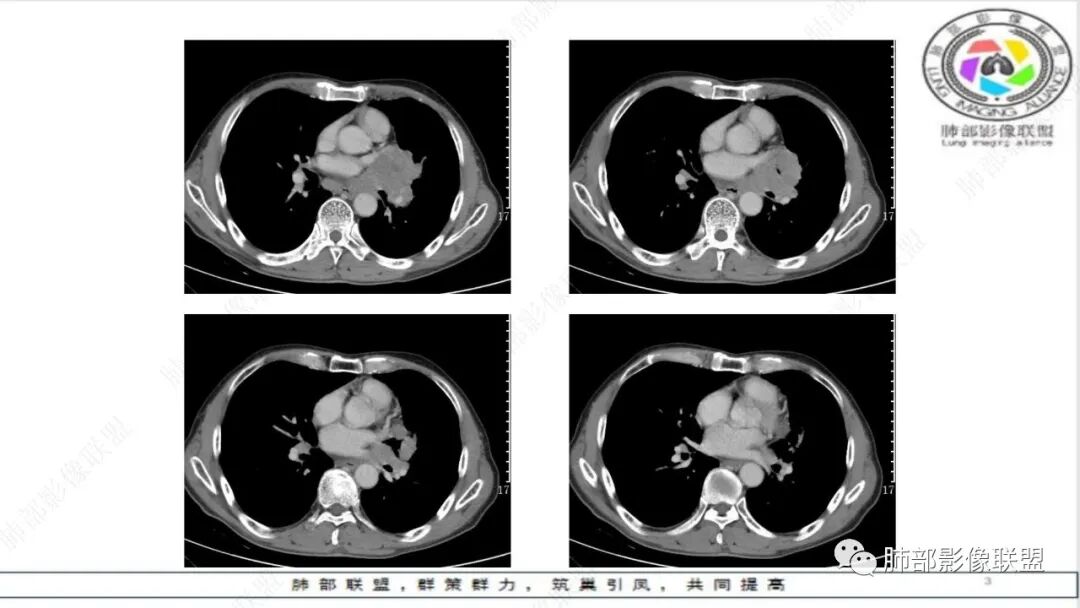

老年男性,肺气肿,左肺门及纵膈多发肿大淋巴结融合,包埋血管,冰冻,左肺上叶支气管受压变窄,左肺上叶胸膜下楔形实变,梗死灶?考虑小细胞癌,鉴别腺癌

纵隔内及左肺门淋巴结肿大,冰冻纵膈,肺动脉包绕受压,支气管受压变窄,呈针孔样。双肺上叶结节及条索考虑陈旧结核。老年男性,慢支肺气肿背景,考虑小细胞肺癌。左肺上叶后段大片实变,不符合小细胞肺癌原发灶,二元论感染灶?肺栓塞?

晨读:男,65,咳喘1月余,加重3天。胸部CT:纵隔、肺门多发淋巴结肿大融合,冰冻纵隔,冰冻肺门,大血管包埋挤压,左肺A主干变窄。平扫密度较均匀,不均匀强化,灶性低密度。右上肺多发实性结节,中轴间质分布;左上叶针孔状支气管,后段胸膜下近楔形斑片影,融冰?考虑Ca,SCLC,并左上叶PTE?鉴别淋巴瘤。

老年男性,肺气肿。影像:冰冻纵膈及肺门,大病灶内小灶状坏死,少部分病灶明显坏死,肺动脉包绕受压,支气管受压变窄,呈针孔样改变。考虑小细胞肺癌,鉴别淋巴瘤,转移瘤。

老年慢性,肺气肿背景,纵隔左肺门明显多发肿大淋巴结且融合,密度相对均匀,增强后轻中度强化,偏纵隔右侧淋巴结坏死明显,左肺支气管可见受压变窄,呈针孔样改变。左肺上叶叶间裂上方山丘状混合磨玻璃病灶,内密度不均可见空泡。考虑小细胞肺癌(娘小崽大)。

冰冻征

血管包埋征

冰冻肺门多于冰冻纵隔,与淋巴引流方向一致,淋巴转移先增值扩大,然后侵犯周围组织

血管包埋时一般均匀变细,提示侵袭力强

脂肪间隙消失-淋巴转移后侵犯到周围脂肪间隙,提示侵袭力强